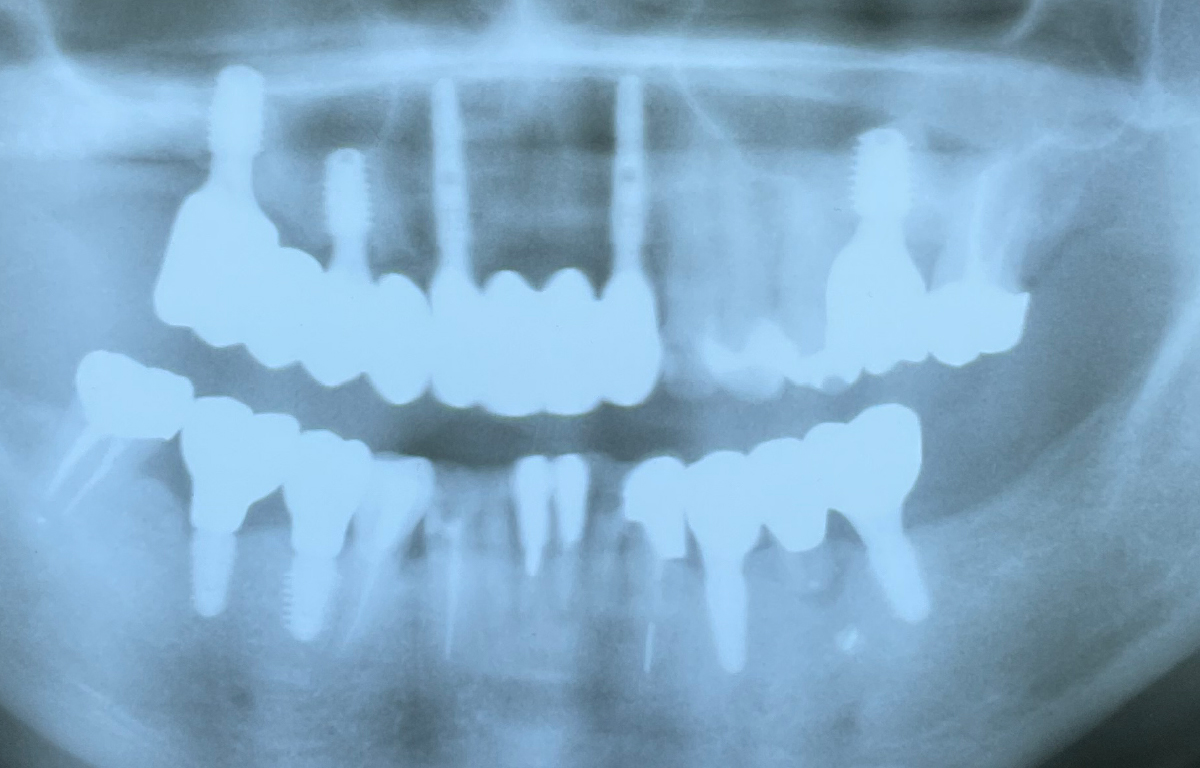

<60歳女性が、顔面麻痺を訴え来院>9本ものインプラントが。打ち過ぎで当院では処置はできないと判断して信頼できる大学病院*を紹介しました。

<86歳女性が来院>経験の浅い、技術のない歯科医師によるインプラント。インプラントが抜けてしまい、右上以外の4本も同じような状況に。信頼できる大学病院*を紹介しました。